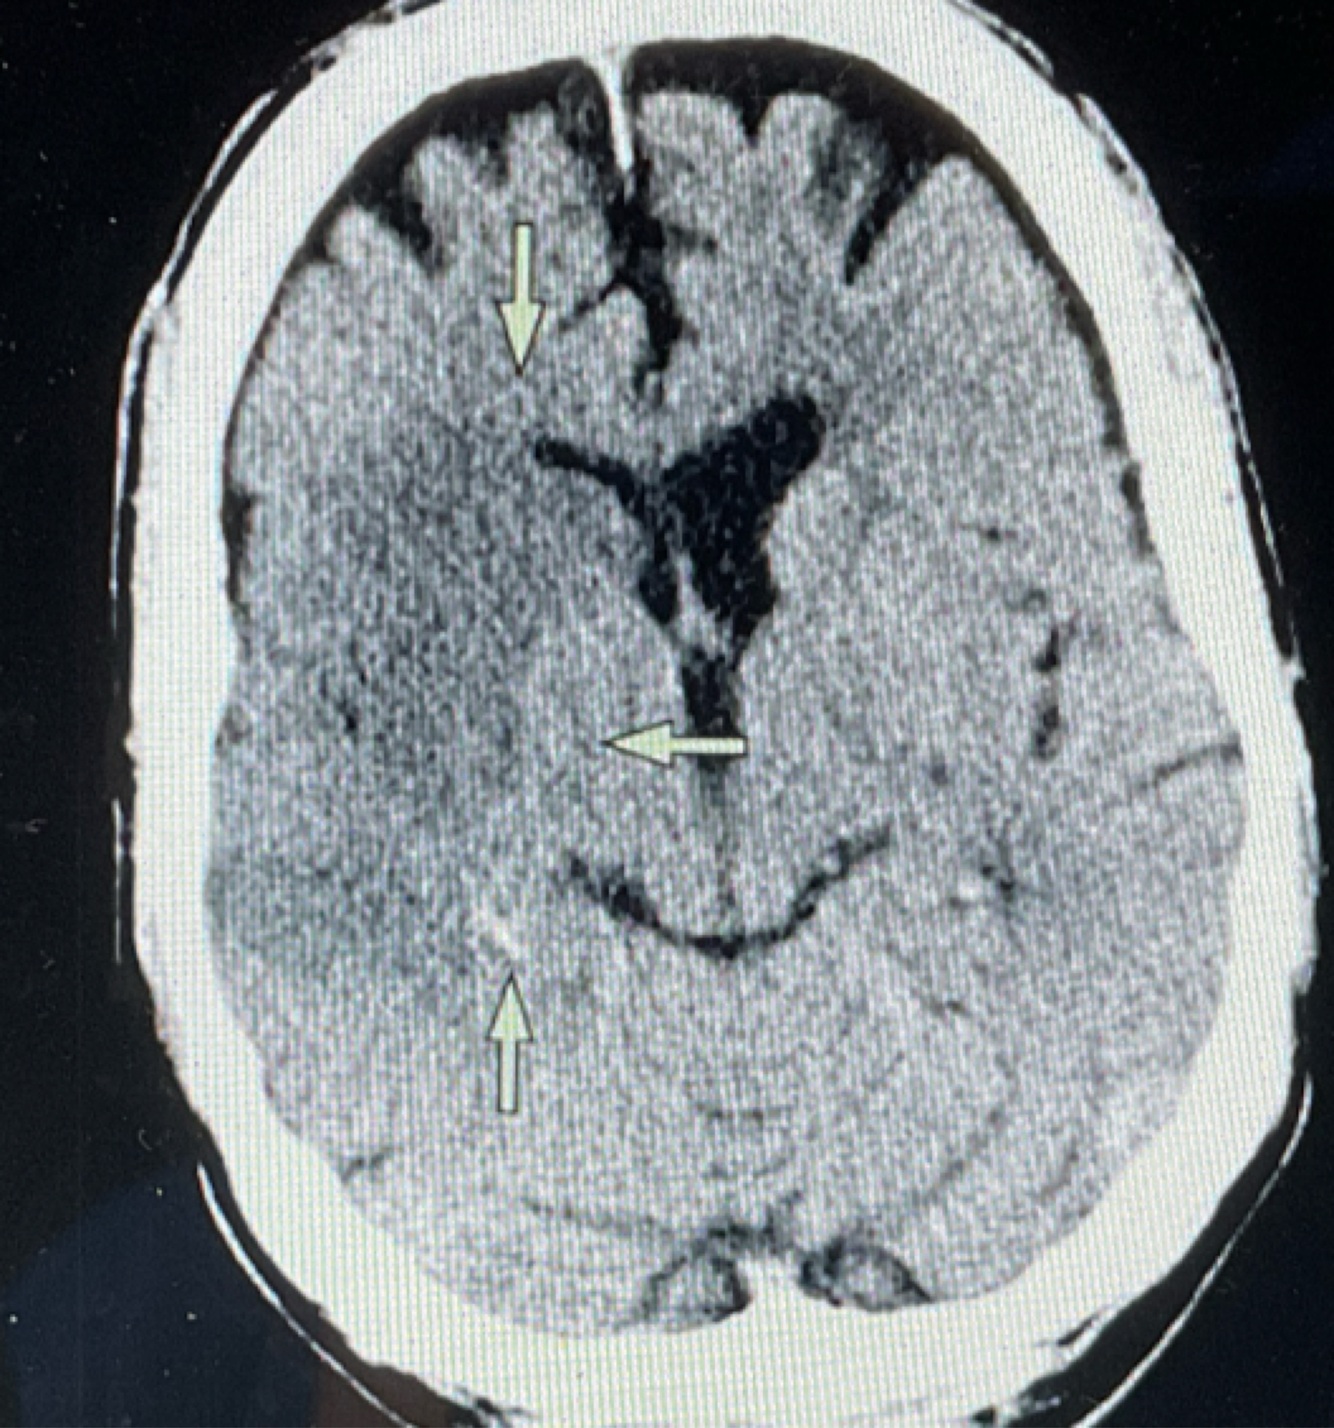

A

EVC isquémico agudo